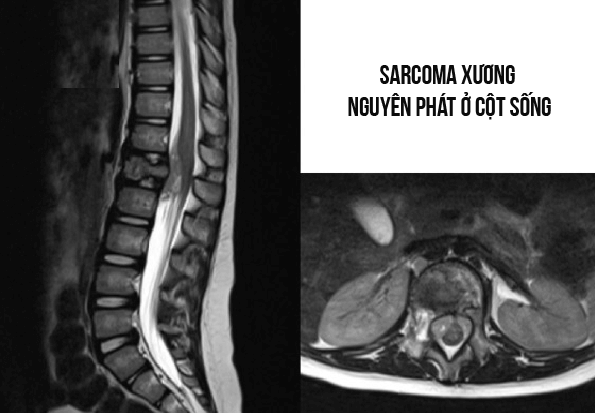

Ba loại sarcoma xương nguyên phát chính ở cột sống là sarcoma xương, sarcoma Ewing và sarcoma sụn. Các khối u này có thể gặp ở bất kỳ đoạn nào của cột sống. Bài viết sau sẽ giải đáp cho các bạn về căn bệnh này.

Sarcoma Ewing cột sống chiếm 5%. Trong sarcoma Ewing có tổn thương xương trục thường gặp nhất ở khung chậu. Ngược với xương dài, phản ứng màng xương và phá hủy dạng thấm là chủ yếu, các tổn thương hủy xương kèm với khối mô mềm ở thân đốt sống là dấu hiệu Xquang chính của tổn thương cột sống do Sarcoma Ewing. Sự nguyên vẹn của đĩa đệm liền kề giúp phân biệt Sarcoma Ewing và viêm cột sống dính khớp.